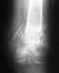

По этому снимку ничего плохого не видно. Нужна и вторая проекция. Когда сделан снимок?

Для того, чтобы предложить конкретный план выхода из этой ситуации, нужно более точное представление о проблеме - надо хотя бы увидеть свежие рентгенограммы всего предплечья в двух проекциях.